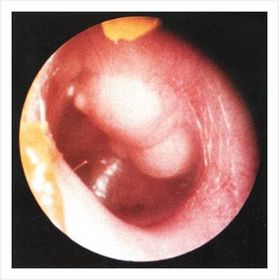

COLESTEATOMA SEGÚN EL EQUIPO

GLOMUS JUGULARE

MASTOIDITIS

OTITIS SEROSA MEDIA

POLIPO AUDITIVO